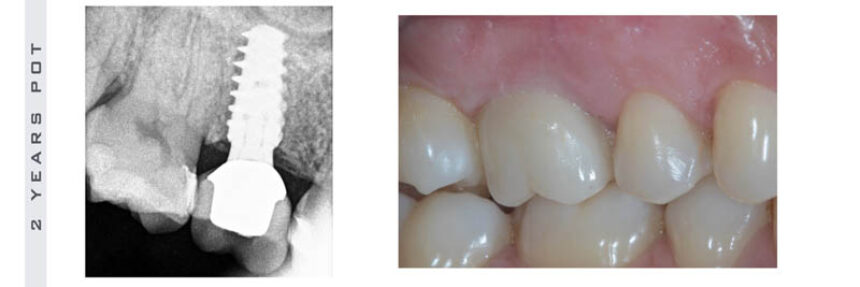

Today one of the biggest problems in Implant dentistry is the increasing prevalence of cases affected by peri-implantitis. The literature shows that up to 20% of our clinical cases might be affected by this disease and any efforts to treat it and achieve long term stability have failed till now. The purpose of this course is to clarify the related risk factors in all aspects of treatment, from case selection to implant placement to prosthesis delivery, and provide simple protocols of treatment that can ensure ideal conditions for long term stable results.

- Ideal Implant Positioning

- Improved restorative protocols